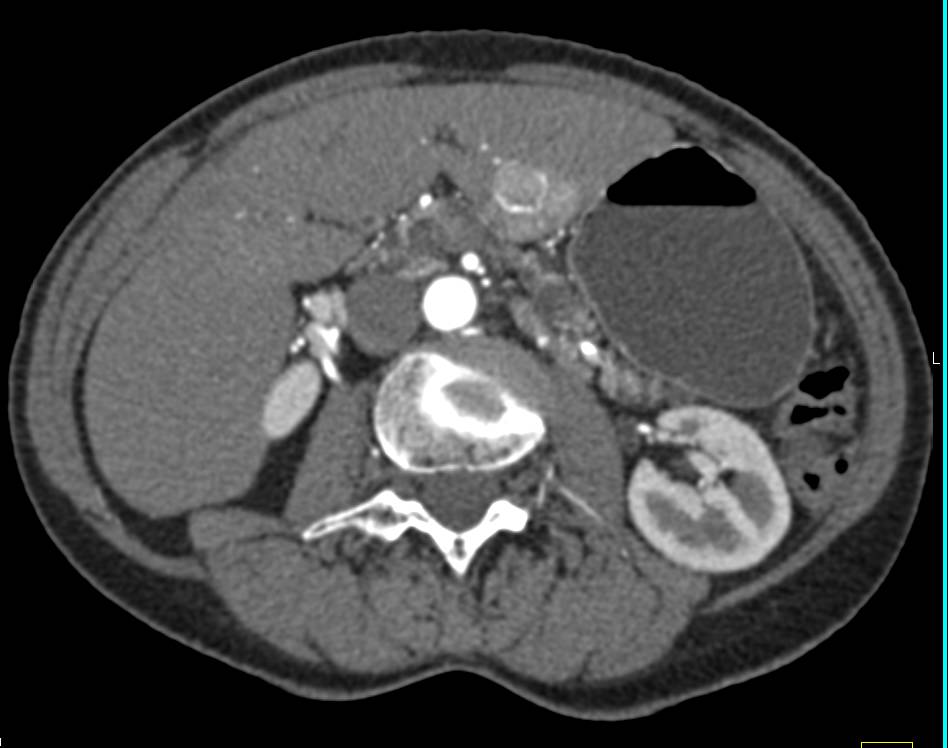

Locally Recurrent Renal Cell Carcinoma with Bone and Muscle Metastases